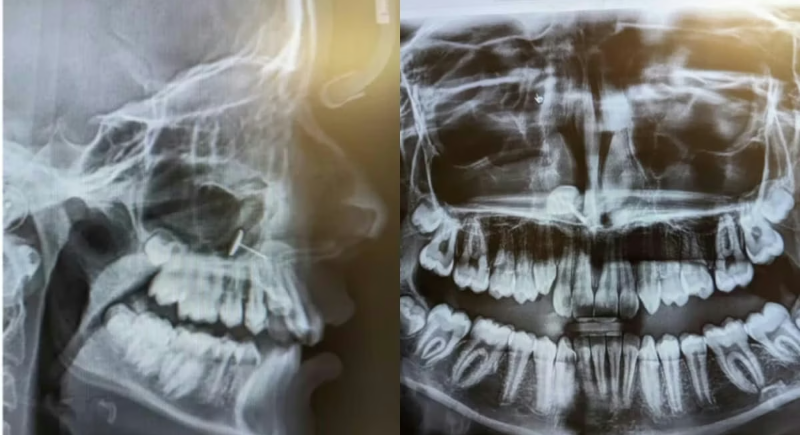

अमेरिका के वॉशिंगटन स्टेट में एक साधारण डेंटल चेकअप ने एक मां और उसकी 13 साल की बेटी के लिए एक हैरान करने वाला अनुभव दे दिया. यह कहानी न केवल मेडिकल मिस्ट्री की तरह सामने आई, बल्कि सोशल मीडिया पर भी वायरल हो गई. आइए जानते हैं कि आखिर क्या था पूरा मामला।अमेरिका के वॉशिंगटन स्टेट में एक साधारण डेंटल चेकअप ने एक मां और उसकी 13 साल की बेटी के लिए एक हैरान करने वाला अनुभव दे दिया. यह कहानी न केवल मेडिकल मिस्ट्री की तरह सामने आई, बल्कि सोशल मीडिया पर भी वायरल हो गई. आइए जानते हैं कि आखिर क्या था पूरा मामला।